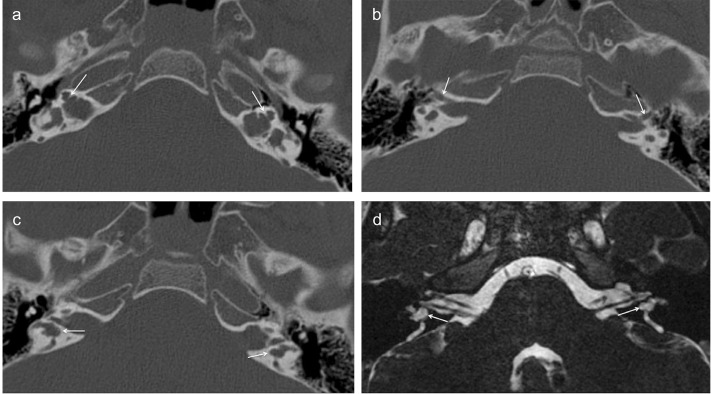

Results: All cases had bilateral IP-III anomaly, bulbous internal auditory canals (IACs), absent bony modiolus with preserved interscalar septa, intact cochleovestibular, and facial nerves. OC thickness was decreased in all cases compared to the control group (p<0.001). In XLD patients, the cochlea had decreased transverse dimension and increased height compared to the control group (p< 0.001). Five patients (38.4%) had bilateral cystic structures adjacent to the vestibule and/or semicircular canals (SCCs). Hypothalamus was thickened or had a lobular appearance in all cases (subtle in one). Additionally, hamartoma-like appearance of the hypothalamus was present in half.

Conclusion: XLD is a rare inner ear anomaly that is frequently associated with hypothalamic malformations. The OC thickness of IP-III patients appears to be decreased with accompanying decreased transverse dimension of the cochlea which could have implications in electrode selection during cochlear implantation. Cystic /diverticular lesions surrounding the vestibule and semicircular canals are also frequently seen but a rarely reported finding.